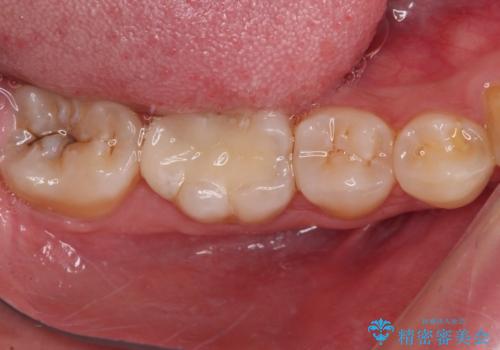

適合の良いセラミック治療は、むし歯再発のリスクが低いです。

目立つ銀歯がなくなり、患者様は大変満足されました。